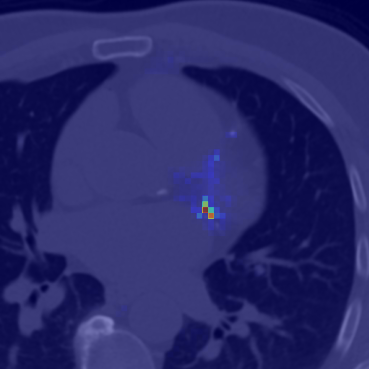

The effectiveness of our label-guided approach is visualized in Figure 4, which compares feature representations generated by standard DINO and DINO-LG models via PCA analysis. The figure shows an original CT slice containing coronary calcification in the left anterior descending artery (a), where the ground truth annotation (b) occupies approximately 0.04% of the image area. Standard DINO features (c) exhibit diffuse activation across cardiac structures, while DINO-LG features (d) demonstrate concentrated activation on calcified regions (bright yellow areas), validating successful feature guidance toward regions of clinical interest. The PCA visualization is applied to 768-dimensional [CLS] token embeddings extracted from the final transformer layer to illustrate how label-guided training directs the model’s attention to task-relevant features.

Refer to caption

(a)

(b)

(c)

(d)

Figure 4: Feature visualization comparison via PCA. (a) Original CT slice. (b) Ground truth annotation. (c) Standard DINO features. (d) DINO-LG features.